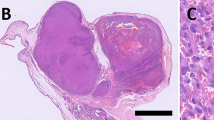

Melanoma is a malignant neoplasm occurring in several animal species, and is the most frequently found tumor in the oral cavity in dogs. Melanomas are classified into two types: melanotic and amelanotic. Prior research suggests that human amelanotic melanomas are more aggressive than their melanotic counterparts. This study evaluates the behavior of canine melanotic and amelanotic oral cavity melanomas and quantifies cell proliferation and the expression of connexins. Twenty-five melanomas (16 melanotic and 9 amelanotic) were collected from dogs during clinical procedures at the Veterinary Hospital of the School of Veterinary Medicine and Animal Science of the University of São Paulo, Brazil. After diagnosis, dogs were followed until death or euthanasia. Histopathology confirmed the gross melanotic or amelanotic characteristics and tumors were classified according to the WHO. HMB45 or Melan A immunostainings were performed to confirm the diagnosis of amelanotic melanomas. Cell proliferation was quantified both by counting mitotic figures and PCNA positive nuclei. Expressions of connexins 26 and 43 were evaluated by immunohistochemistry, qRT-PCR and Western blot. Dogs bearing amelanotic melanomas presented a shorter lifespan in comparison to those with melanotic melanomas. Cell proliferation was significantly higher in amelanotic melanomas. Expressions of Connexins 26 and 43 were significantly reduced in amelanotic melanomas. The results presented here suggest that oral cavity melanotic and amelanotic melanomas differ regarding their behavior, cell proliferation and connexin expression in dogs, indicating a higher aggressiveness of amelanotic variants.